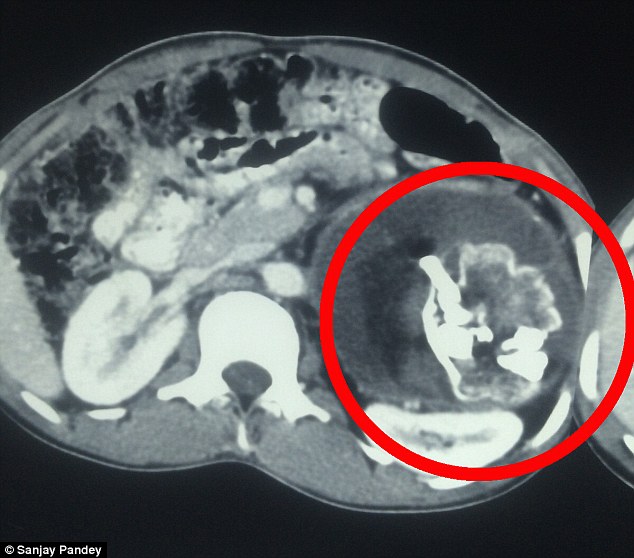

Narendra Kumar, sem er 18 ára gamall, var fluttur í hasti á Swaropp spítalann í indverska bænum Uttar Pradesh, sem er staðsettur í norðurhluta Indlands sökum þrálátra magaverkja sem ullu þrálátu þyngdartapi, krónískum uppköstum og gífurlegum sársauka. Í fyrstu var ekki vitað hvað olli verkjunum, en eftir talsverðar rannsóknir leiddi sneiðmyndataka og röntgenmyndir í ljós að drengurinn gekk með æxli í maganum, sem var 20 cm í þvermál og vó 2.5 kíló að þyngd.

Æxlið reyndist vera fósturvísir að vansköpuðum tvíburabróður Narendra og samanstóð af beinmassa, talsverðum hárvexti og risavöxnum tönnum, sem höfðu þroskast afbrigðilega í maga unga mannsins.

Um gífurlega sjaldgæft heilkenni er að ræða sem í læknisfræðinni nefnist fetus in fetu og, en slíkt gerist þegar eitt fóstur gleypir systkini sitt meðan á meðgöngu stendur. Sá tvíburinn sem er gleyptur af hinum, nærist á þeim næringarefnum sem hýsillinn veitir, en afmyndaða fóstrið hreiðrar venjulega um sig í maga hýsilsins, þó einnig séu dæmi þess að slíkir tvíburar hafi vaxið í höfuðkúpu systkina sinna og jafnvel í náranum.

Við fjarlægðum það sem mætti kalla vanskapaðs fósturs sem tæknilega var enn á lífi. Fóstrið var þakið hári, var með gífurlega langar tennur og illa þróað höfuð, vísi að bringu og hrygg en líkamsmassinn sjálfur samanstóð af gulum vökva sem líktist legvökva þeim sem myndast í líknarbelgnum.